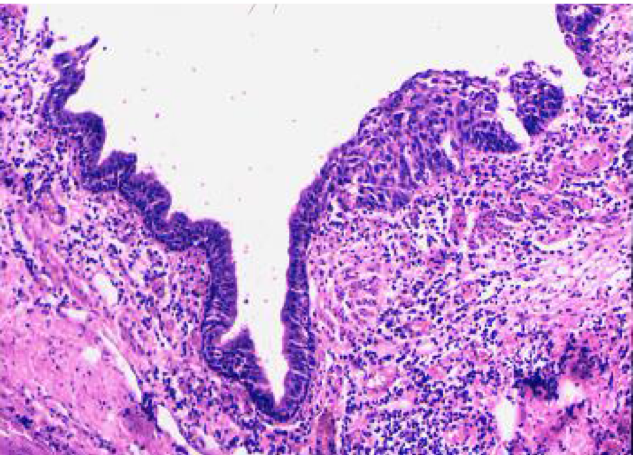

4. 病理变化

病变常起始于较大的支气管,各级支气管均可受累。主要病变为黏膜上皮损伤与修复性改变,支气管黏膜腺体肥大、增生、黏液腺化生以及支气管壁其他组织的慢性炎性损伤。

(1)黏膜上皮的损伤与修复 支气管黏膜上皮纤毛发生粘连、变短、倒伏,甚至缺失,上皮细胞变性、坏死、脱落,在再生修复时可伴有鳞状上皮化生。

图1-2